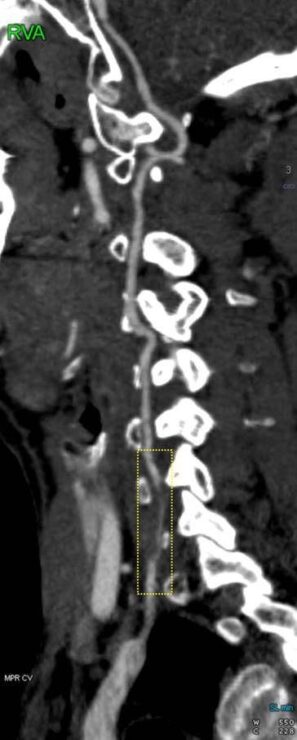

בן 33 מירושלים הגיע למיון בשערי צדק לאחר שסבל מסחרחורות וחולשה בידו הימנית. בדיקת סי טי אנגיו ראש-צוואר שבוצעה באופן מידי חשפה אוטם קטן בחלקו השמאלי של המוחון וקרע בעורק הימני הורטבראלי שמוביל דם לגזע המוח, שזוהו על ידי הרדיולוג התורן, ד"ר סלבה ויאצ'סלב. בשל חוסר התאמה של הממצאים במוחון לממצאים בצוואר בוצעה בדיקת MRI שהדגימה קרע דו צדדי בצרבלום.

ד"ר יואל כהן, נוירולוג בכיר במחלקה לנוירולוגיה במרכז הרפואי שערי צדק שטיפל במקרה מסביר כי מדובר בתופעה שקורית בדרך כלל בצעירים ועלולה להיגרם על ידי פציעות טראומה, חבלה, תאונת דרכים ובעקבותיהן תנועת הצלפת שוט של עמוד השדרה, או בגילאים מבוגרים יותר על ידי גורם דלקתי, ארתריטיס, והפרעה ברקמת החיבור. קרע דו צדדי משויך לעיתים למטופלים עם רקע לבבי. משנשללה הסיבה הלבבית והמטופל שלל רקע של מחלת עורקים או פציעת טראומה, התעלומה הועברה לרדיולוגים לבירור.

ד"ר אלי בן דוד. רדיולוג בכיר שפתר את התעלומה מספר כי קרע דו צדדי ורטבראלי הוא הממצא המובהק ביותר בפציעות ראש צוואר. אלו לא הותירו הרבה מקום לספק, השאלה שנשאלה לא הייתה האם המטופל קיבל חבלה אלא מתי. "עשינו שקלול של כל הגורמים – אין רקע דלקתי ובעיות ברקמת חיבור – לאחר בדיקות דם ששללו גורם דלקתי ולאחר בדיקת MRI מתקדמת הגורם היחיד שהיה סביר הוא פציעת טראומה. ביקשתי לערוך תשאול חוזר, ואכן בשיחה חוזרת עם הנוירולוגים נזכר המטופל כי כשבועיים לפני האירוע, נהג במסלול ׳מכוניות מתנגשות׳ וחווה פציעת ׳צליפת שוט׳ שאופיינית לתאונת דרכים. הבנת המנגנון חשובה לקבלת טיפול מתאים. אחרת יש פוטנציאל לסכנת חיים. לעיתים קרובות אנו מקבלים הפניות מהמיון שהן לא אינפורמטיביות מאוד – אך למעשה ההדמיה מכוונת לסיפור האמתי". מדגיש ד"ר בן דוד.